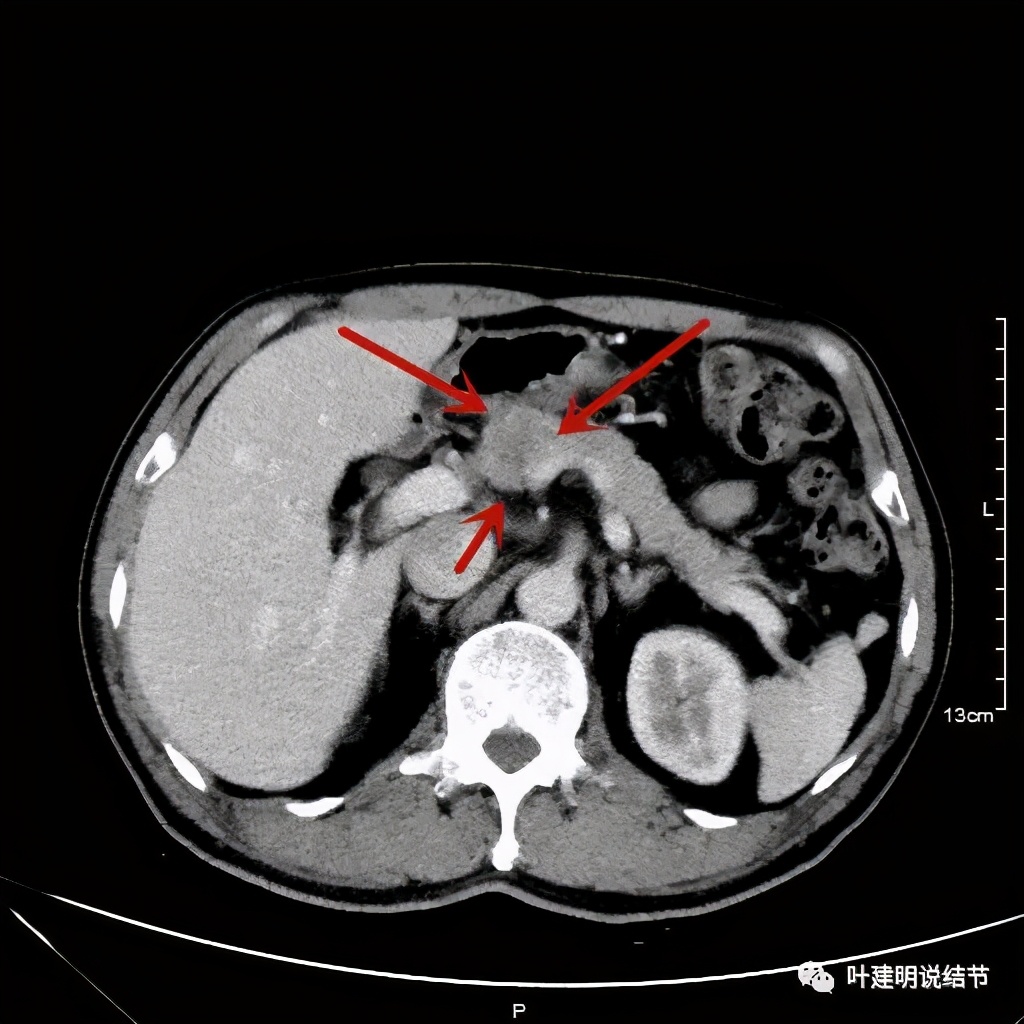

右肺中叶与胰腺均考虑恶性肿瘤,但胰腺占位摄取只轻度增高。CT图像如下: